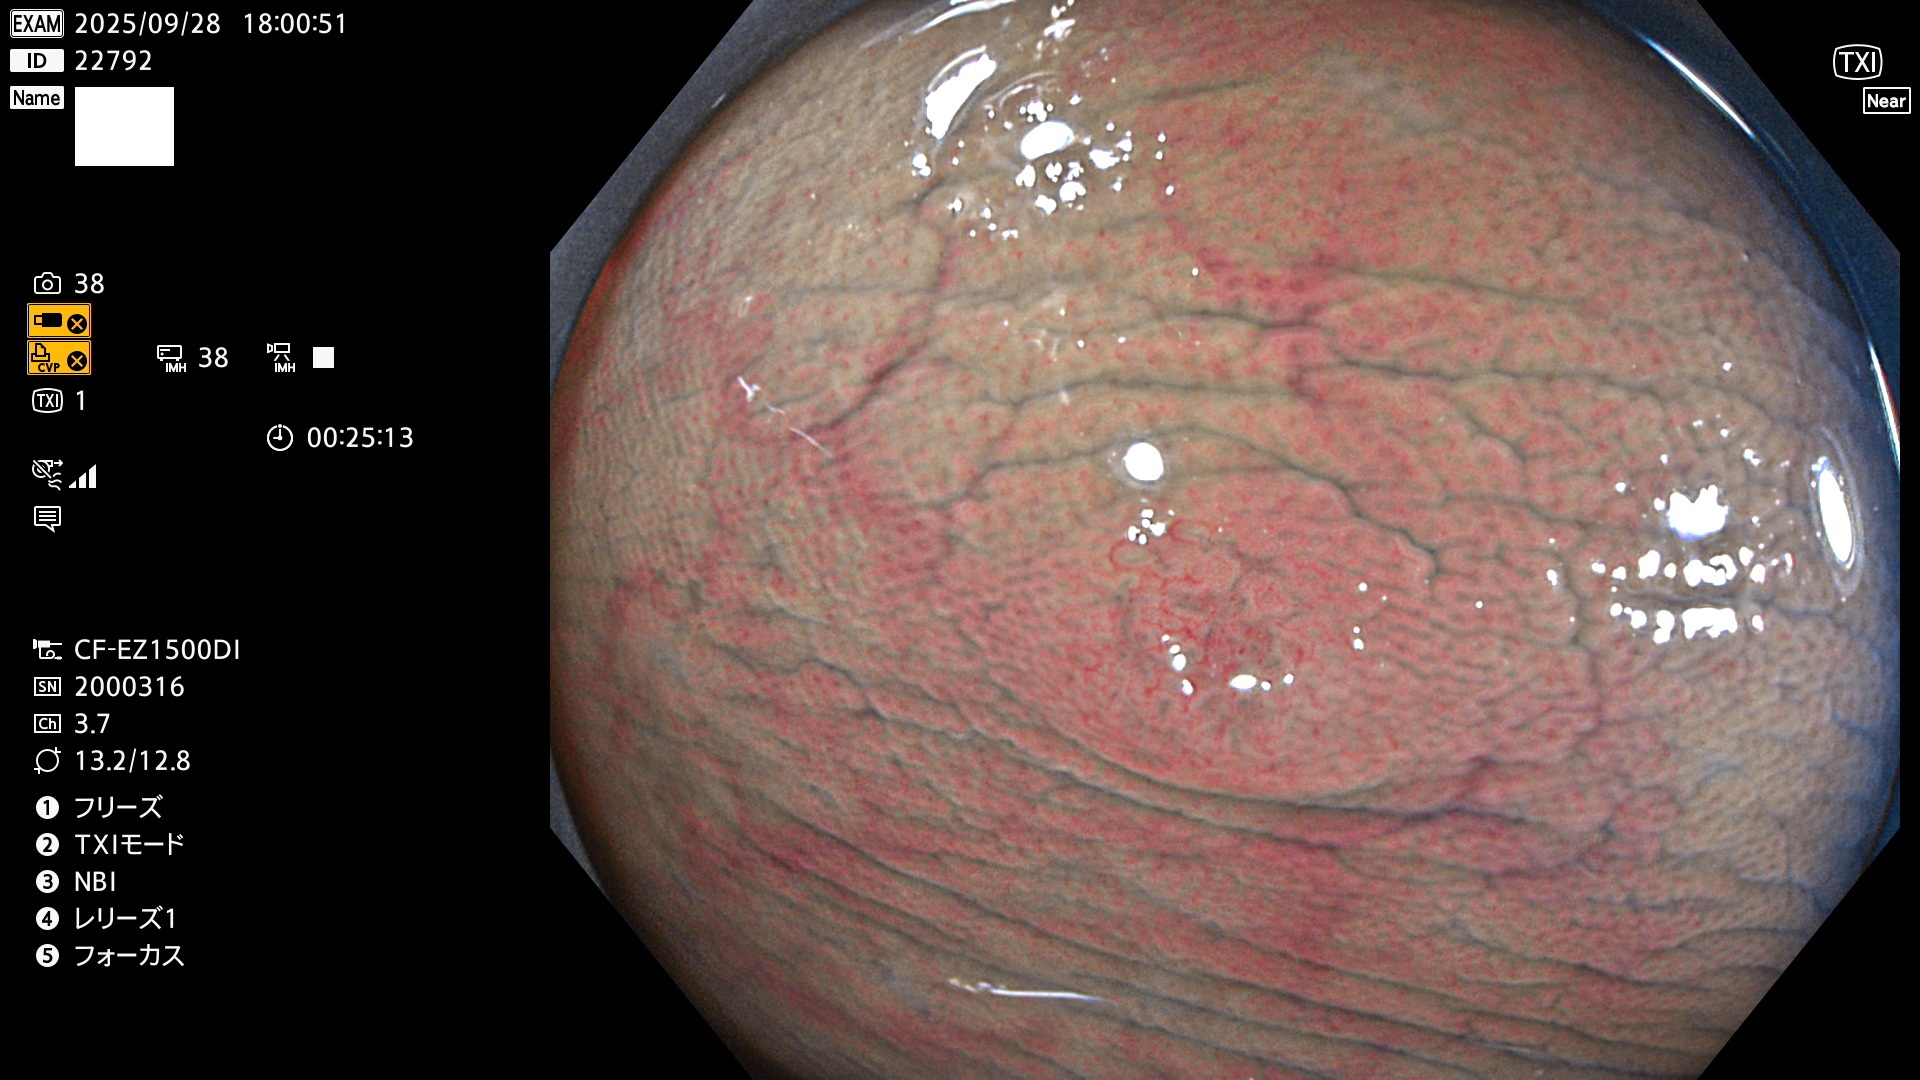

2025年9月25日〜9月28日の4日間(40件)4個 (Uc_ADR=4個/40人=10%)

2025年9月25日〜9月28日の4日間(40件)で4個 (Uc_ADR=4個/40人=10%)